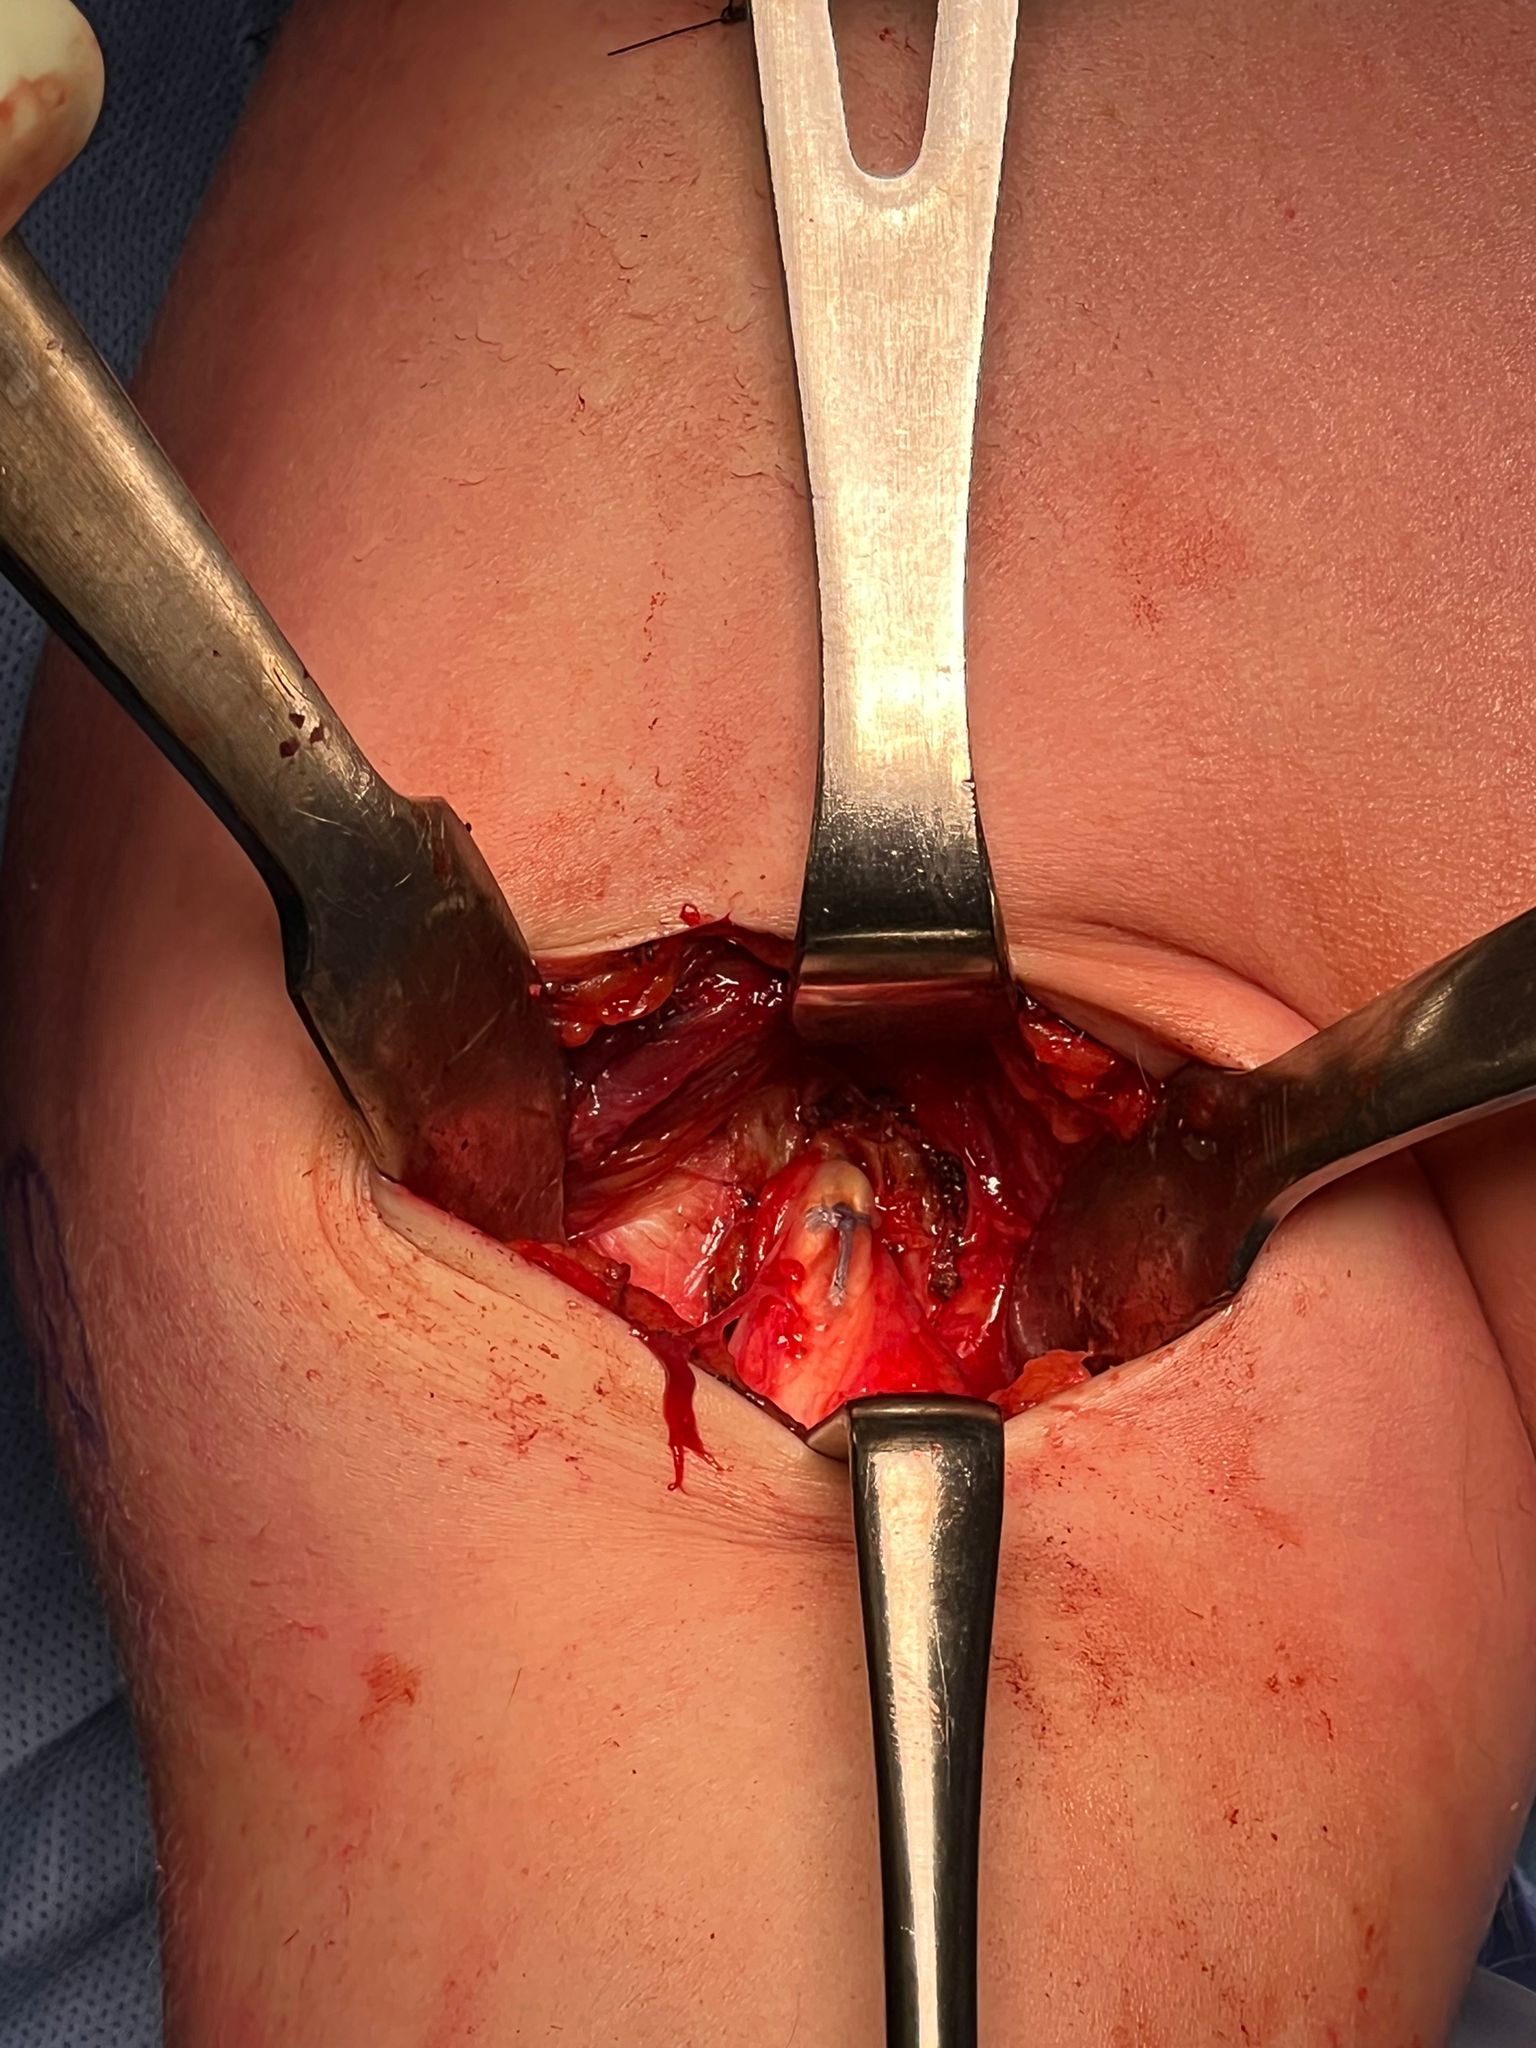

- incision centered on humerus below pectoralis tendon

- retract deltoid laterally / elevate pectoralis tendon / conjoint tendon medially

- find biceps tendon / shorten to 2cm of tendon / suture

- anchor biceps tendon

Bicortical open subpectoral biceps tenodesis using Arthrex Biceps Button